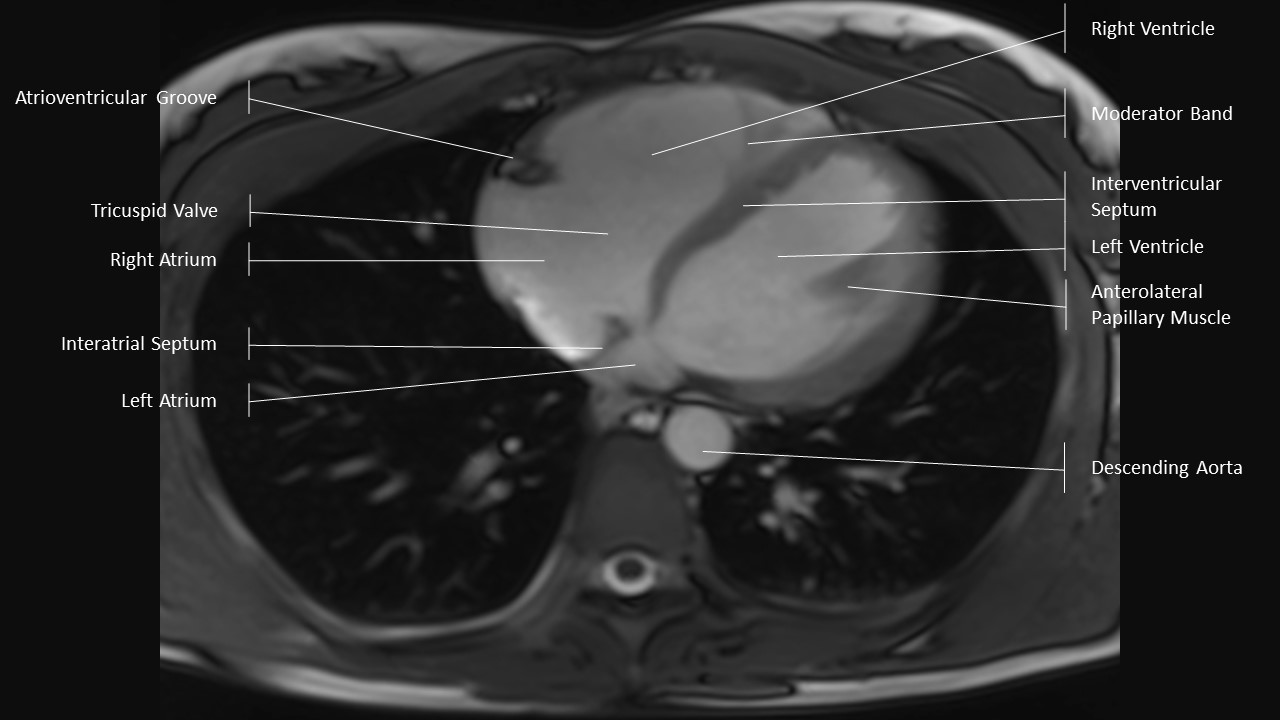

Axial Series

Extracardiac Labels